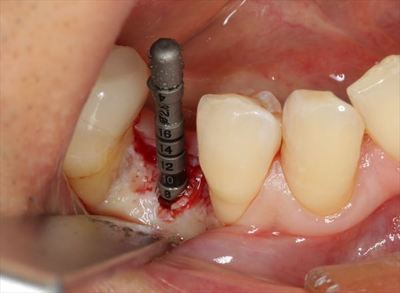

局所麻酔後に安全な深度までドリリングして深度ゲージを挿入しレントゲンを撮影します。

予定通りでしたのでこのままドリルステップを進めます。